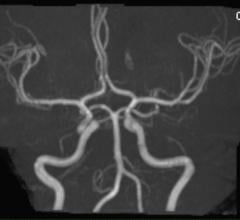

Whole-body magnetic resonance angiography (MRA) found a surprisingly high prevalence of atherosclerosis in people considered at low to intermediate risk for cardiovascular disease, according to a study appearing online in the journal Radiology. Almost half of all study participants had at least one narrowed artery.